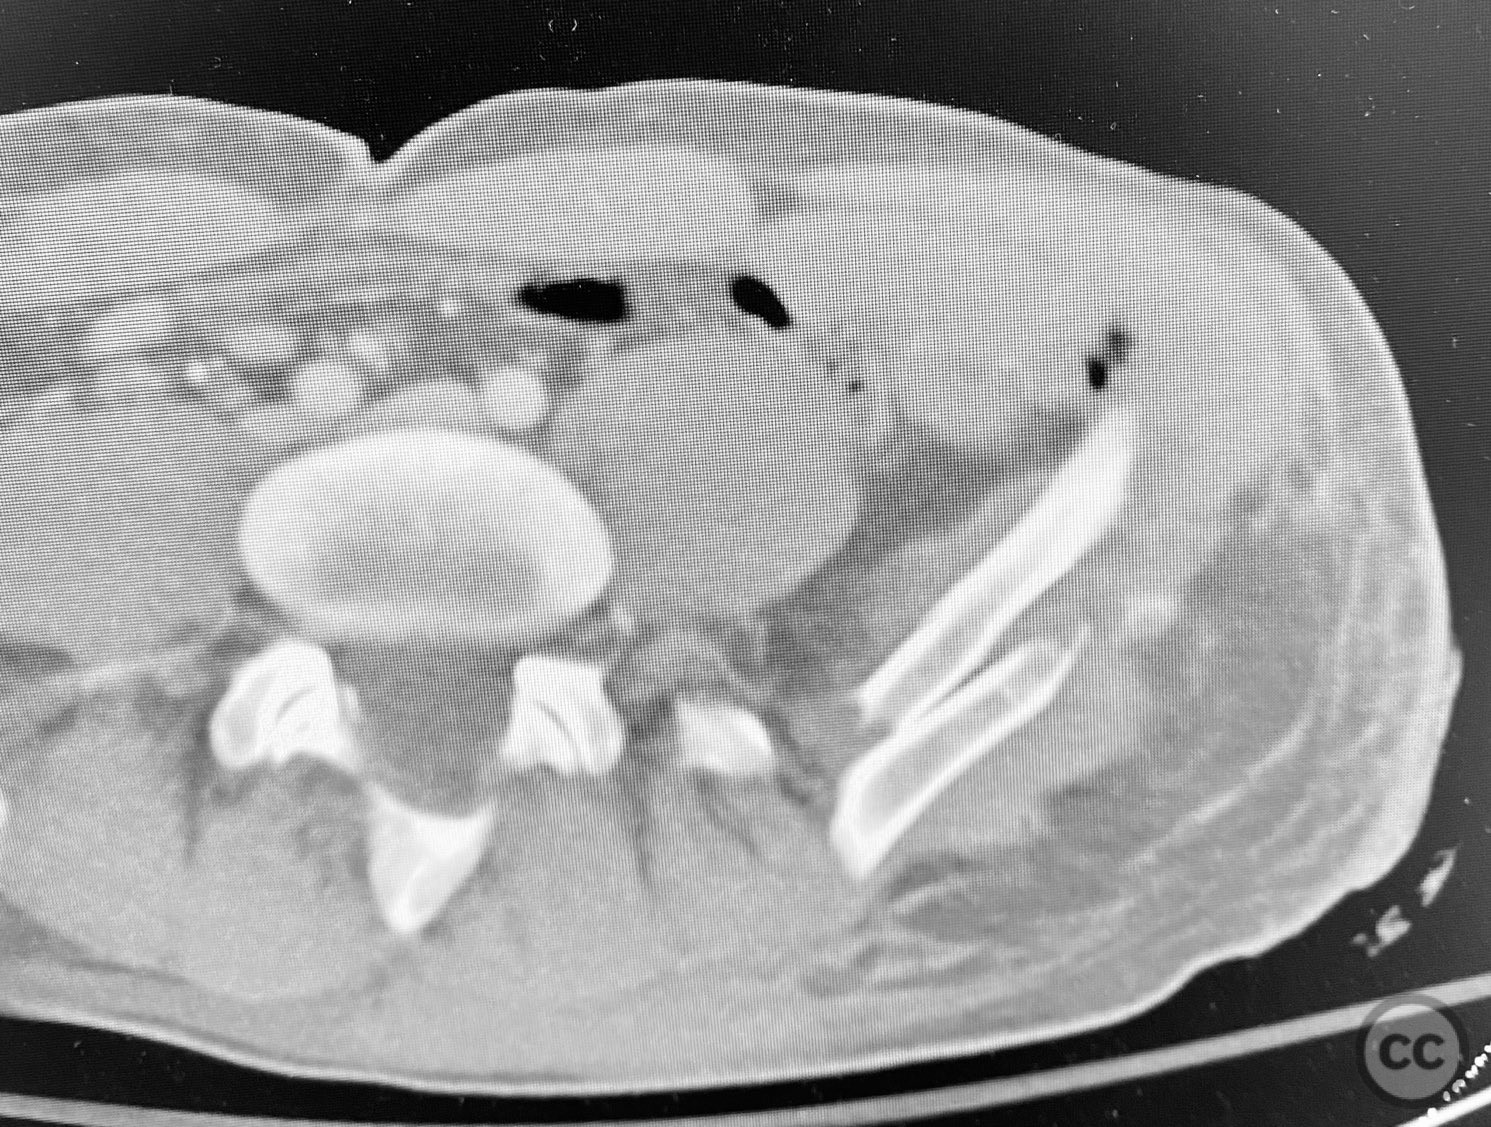

Clinical and radiological findings:  A patient sustained a high-energy injury resulting in an open, comminuted fracture of the iliac wing, sparing the pelvic ring. Associated injuries included spine, rib, and femur fractures. Initial radiographs and axial CT imaging demonstrated significant comminution of the iliac wing with intraosseous air densities indicative of an open wound. No pelvic ring disruption was identified. AO/OTA classification: 61-A2. The presence of multiple associated injuries is consistent with a direct lateral load mechanism.